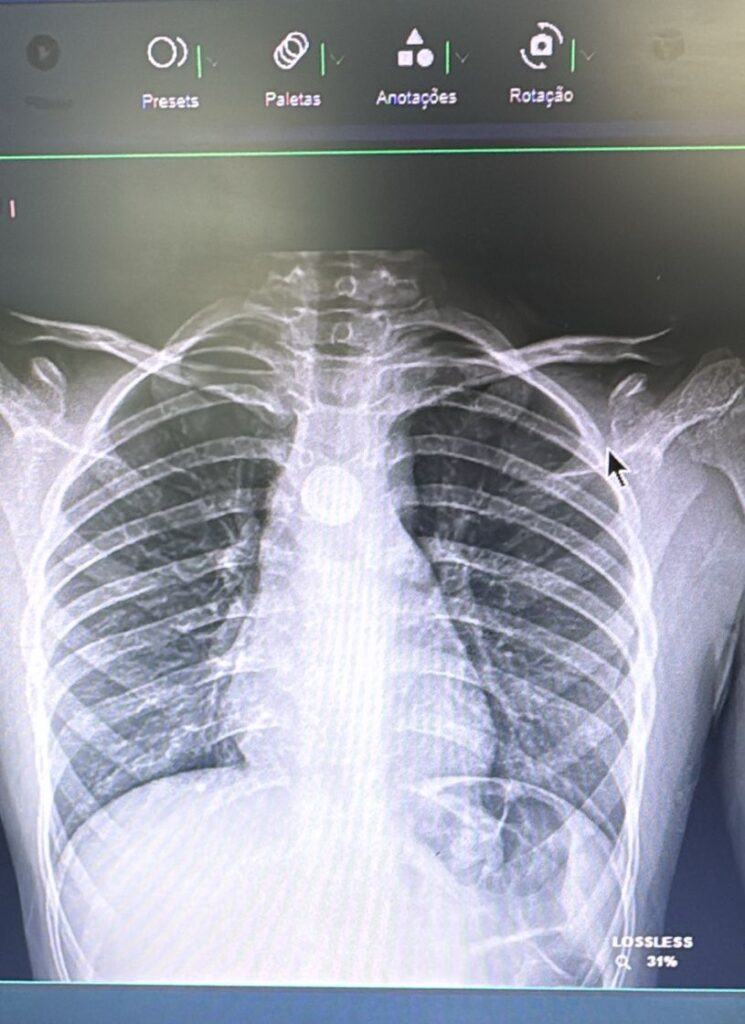

A identificação da broncoaspiração nas crianças, principalmente quando os pais não percebem, é algo desafiador e vai exigir do profissional de saúde expertise para solicitar exames de imagem que ajudarão no diagnóstico.

“O grande risco é quando o corpo estranho fica alojado no esôfago, local com mais sintomas e risco”, explica Giovana Tuccille Comes Brambilla, cirurgiã pediátrica do HCFMB. Segundo a especialista, o raio-x simples é o exame capaz de identificar a presença de um corpo estranho.